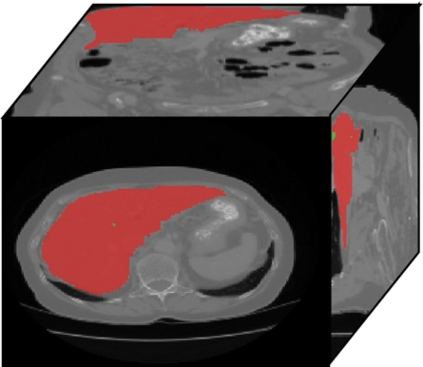

UNet and its variants have been widely used in medical image segmentation. However, these models, especially those based on Transformer architectures, pose challenges due to their large number of parameters and computational loads, making them unsuitable for mobile health applications. Recently, State Space Models (SSMs), exemplified by Mamba, have emerged as competitive alternatives to CNN and Transformer architectures. Building upon this, we employ Mamba as a lightweight substitute for CNN and Transformer within UNet, aiming at tackling challenges stemming from computational resource limitations in real medical settings. To this end, we introduce the Lightweight Mamba UNet (LightM-UNet) that integrates Mamba and UNet in a lightweight framework. Specifically, LightM-UNet leverages the Residual Vision Mamba Layer in a pure Mamba fashion to extract deep semantic features and model long-range spatial dependencies, with linear computational complexity. Extensive experiments conducted on two real-world 2D/3D datasets demonstrate that LightM-UNet surpasses existing state-of-the-art literature. Notably, when compared to the renowned nnU-Net, LightM-UNet achieves superior segmentation performance while drastically reducing parameter and computation costs by 116x and 21x, respectively. This highlights the potential of Mamba in facilitating model lightweighting. Our code implementation is publicly available at https://github.com/MrBlankness/LightM-UNet.